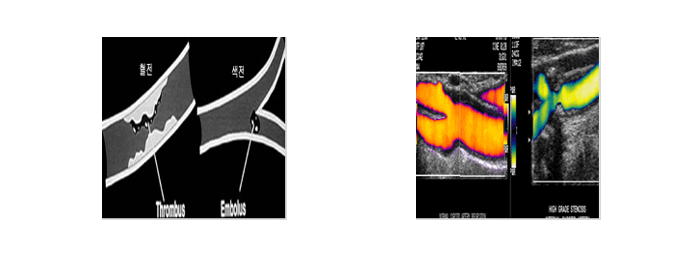

뇌졸중종류

뇌출혈(모야모야병,뇌동맥류,고혈압성 뇌출혈, 뇌동정맥기형 등)뇌경색(혈전성,색전성,열공성)

6. 경동맥 초음파(Carotif U/S)